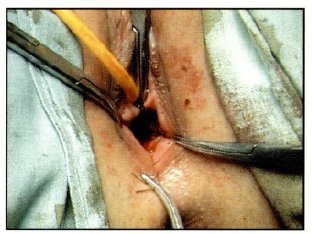

Se drena 1000 cc de liquido de color achocolatado que corresponde a tejido menstrual retenido; se realiza un lavado exhaustivo de la cavidad vaginal mas la colocación de puntos en la mucosa y la fascie vaginal de ambos extremos, proximal y distal, dejando un orificio aceptable de 2 cm. de diámetro; se coloca un tapón vaselinado, que se retira al día siguiente; manteniéndose con soluciones parenterales por 24 horas y antibióticoterapia por 7 días, fue dada de alta al tercer día con evolución favorable e indicación de dilatación diaria con su dedo medio lubricando con bacitracina en crema (Fig: 5, 6, 7, 8).

Fig 7: Resección completa de Tabique Transverso

Fig 8: Sutura entre Mucosas y Fascies Proximal y Distal